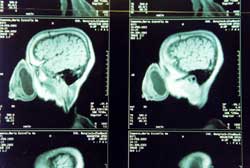

Kernspinbild von Marias Kopf. |

Im

Klinikum Köln-Merheim operierten die Professoren Dr. Jürgen Menzel

(Neurochirurg) und Dr. Dr. Gerald Spilker (Plastischer Chirurg) im Sommer

2002 erfolgreich die Aeta-Frau.

Ich fotografierte während der OP. |